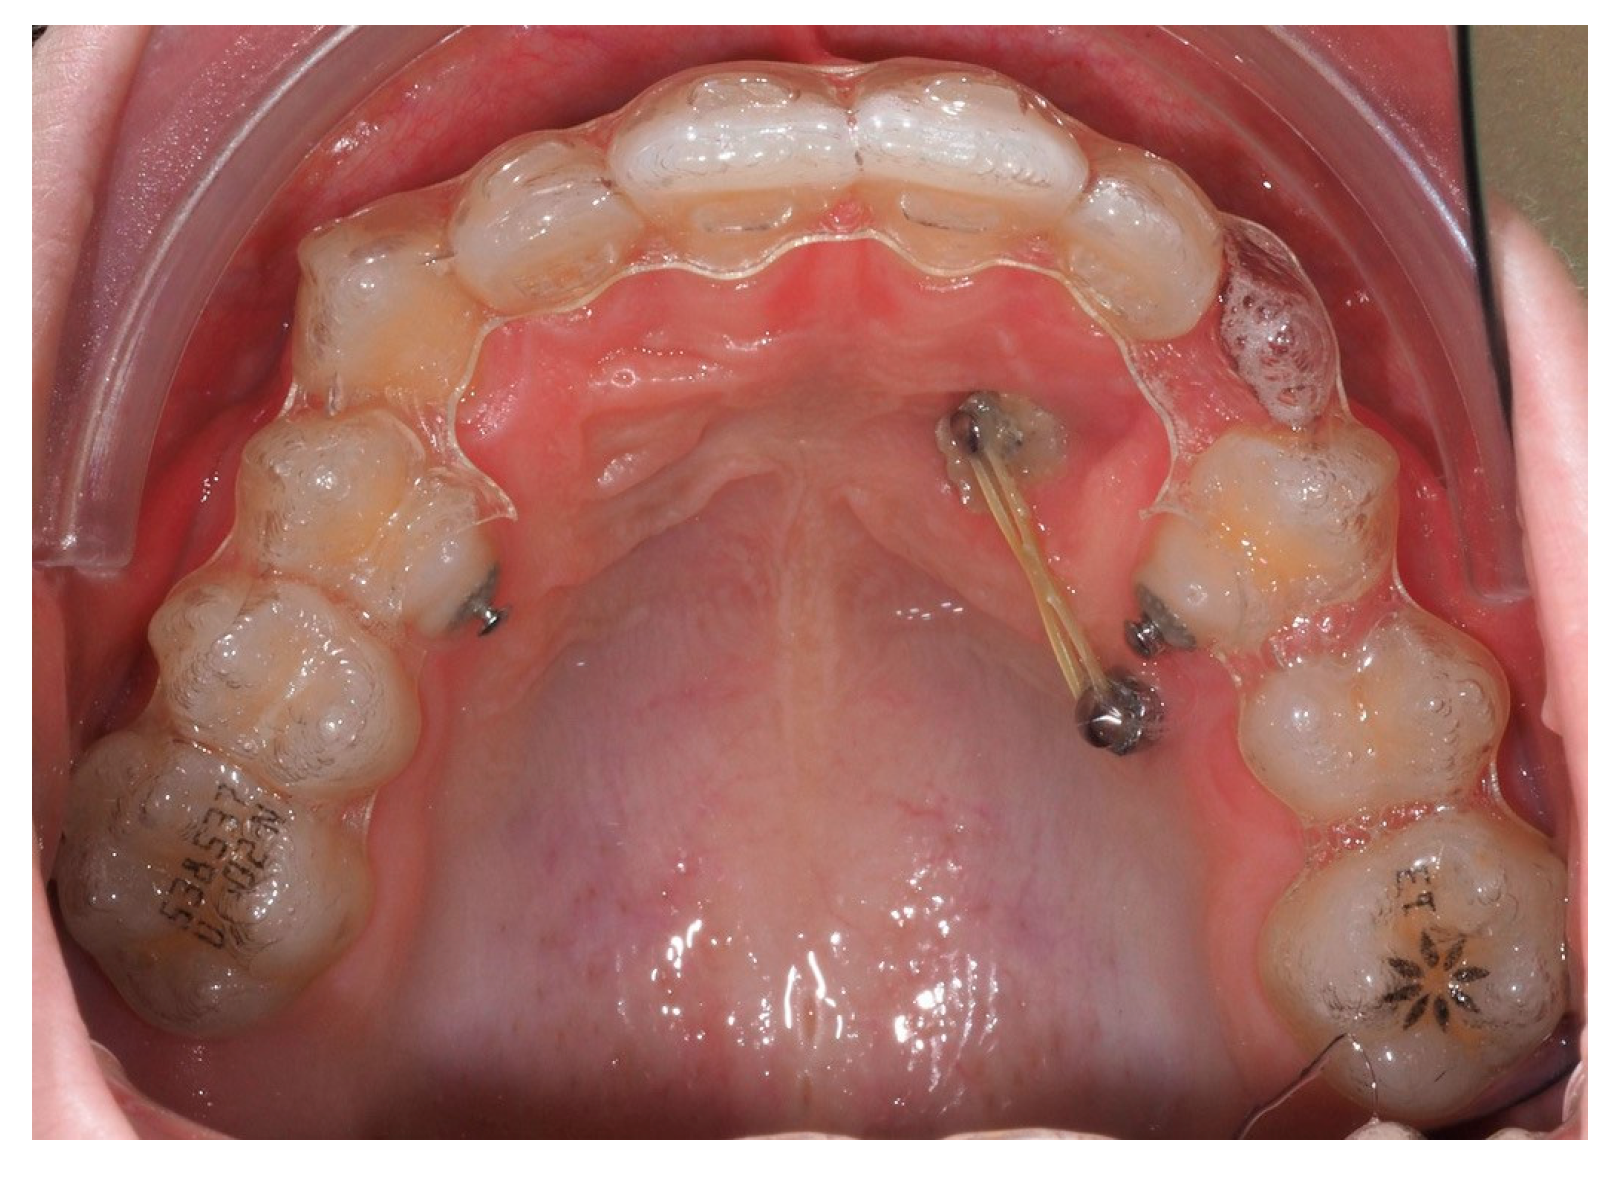

Approximately 7 months later, a palatal mini-implant was placed between teeth 24 and 25, serving as stable anchorage for distal traction using an elastic chain, which was replaced monthly (Figure 15). This movement positioned the canine away from the lateral incisor root. Aligners were customized and adjusted throughout treatment.

Figure 15.

Adjusted aligners, palatal mini-implant, and elastic chain used for distalizing the canine; 7 months after the surgery.